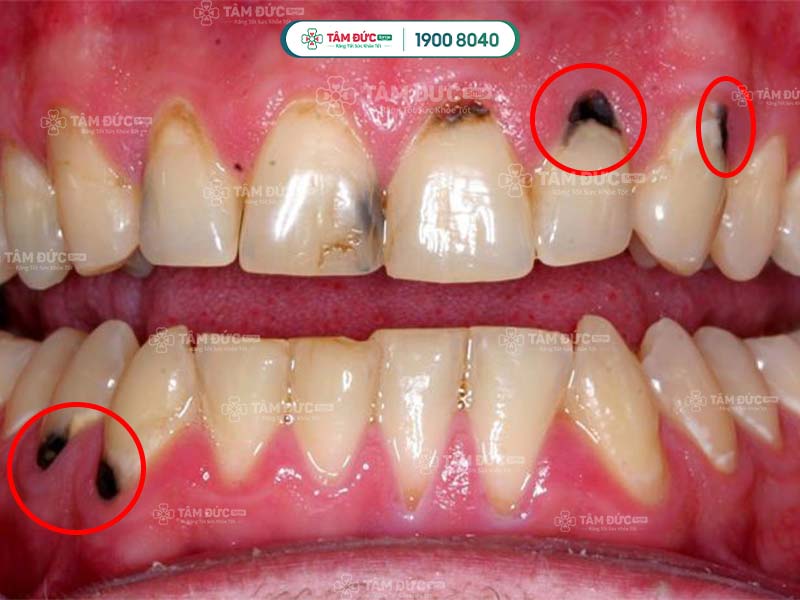

Cao răng bị đen cơ bản là cao răng thông thường, nhưng bị biến đổi màu sắc từ vàng nhạt sang đen do nhiều nguyên nhân. Điều này làm ảnh hưởng sức khỏe răng miệng và thẩm mỹ nụ cười. Cao răng đen hình thành ở thân răng hoặc chân răng, vùng tiếp xúc giữa răng và nướu.

Quý khách không thể loại bỏ cao răng đen bằng cách chải răng thông thường, mà cần đến nha khoa để được hỗ trợ. Không xử lý cao răng kịp thời sẽ làm tổn thương nướu, gây chảy máu chân răng và nhiều vấn đề khác.

cao răng bị đen

2.4. Do sâu răng

Cao răng làm cho bề mặt răng xuất hiện những lỗ nhỏ li ti. Nếu Quý khách không điều trị sâu răng kịp thời, các lỗ li ti lan rộng và làm cho cao răng biến thành màu đen.

cao răng đen quanh chân răng

Cao răng bị đen là dấu hiệu cảnh báo sâu răng đang tiến triển